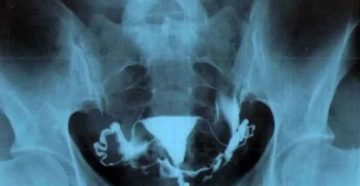

Рентген маточных труб: назначение и особенности проведения процедуры Гистеросальпингография (ГСГ) или метросальпингография (МСГ) называется диагностическое…